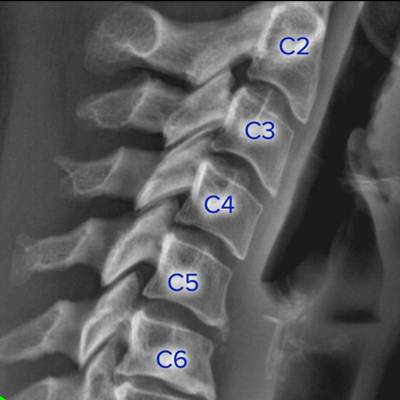

X-rays are primarily used in the medical and dental field. Some of the more common X-rays are done for broken bones and fractures, swallowed items, damage to bones from arthritis, and lung infections. X-rays are also used in a CT scanner, or computed tomography. This modality uses multiple X-rays during one scan, to give a layer-by-layer image. X-rays are also being used in non-medical areas, like airport security and by NASA in outer space.